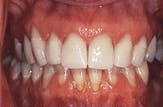

This case illustrates the importance of involving the laboratory as a member of the dental team. In addition to building a team approach, we achieved a new approach to patient service. We were able to use the expertise of clinical dentistry and dental technology to take someone who had been disappointed by dentistry and change her belief of what dentistry can do. She stated that she never knew that dentistry could be like this, and she felt that she had worked with a team of professionals who were committed to giving her the very best (Figures 8 and 9). She has since become a missionary for dentistry. Actively involve your laboratory technicians, and your patients will love the results.

Figure 8

Figure 9